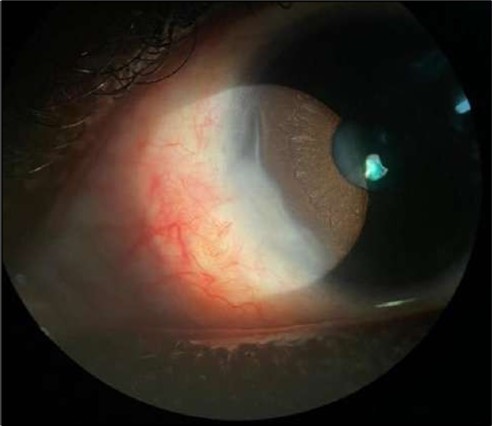

On the current presentation, Snellen VA was 6/6 in the right eye and 6/9 in the left eye, with normal IOP. The left eye demonstrated mild upper lid edema and intense nasal ciliary injection. Slit-lamp evaluation revealed a crescentic area of stromal corneal melting between 7 and 10 o’clock nasally, with overhanging edges and a fluorescein-positive base. No corneal infiltrates were present, and the surrounding stroma remained clear. The anterior chamber was deep and quiet, lens was transparent, pupil was round and reactive & normal posterior segment. Anterior segment optical coherence tomography (AS-OCT) confirmed a localized ulcer, measuring 1324 µm in horizontal width and extending to a depth of 380 μm, compared with an adjacent healthy corneal thickness of 824 µm, corresponding to approximately 46.1% stromal thinning (Figure 1a, Figure 1b, Figure 1c)

Figure 1a.Left eye (OS), on presentation. Slit-lamp image: crescent-shaped peripheral corneal ulceration located nasally, with severe adjacent conjunctival injection, peripheral thinning, and stromal infiltration.